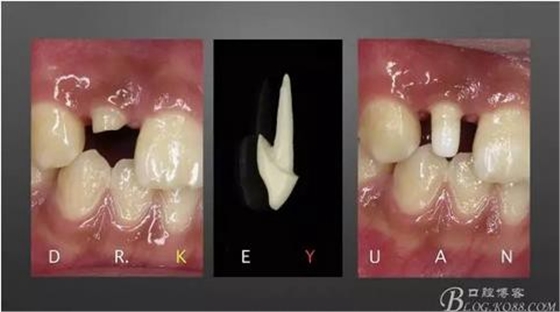

7、最終爭取了2周的時間,能看到牙齦有明顯的改善

8、排齦、硅橡膠第二次取模制作氧化鋯全瓷冠

9、完成最終修復(fù)體

10、復(fù)診試戴最終修復(fù)體(又爭取了2周的時間,再加上技師對最終修復(fù)體鄰接關(guān)系的設(shè)計,牙齦恢復(fù)效果明顯)

11、牙齦狀況對比(有時候你把患者約的時間太長,他可能會不理解你,約著約著就再也約不過來了,有些時候患者的修復(fù)熱情和臨床的治療程序可能成反比,我們要做金玉其外、金玉其中的修復(fù),實難取舍)